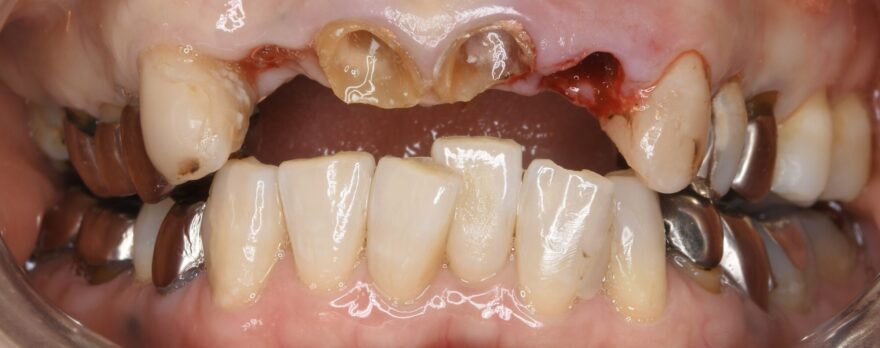

初診時の口腔内写真

銀歯の中が虫歯になっていることがわかります。

こちら側の銀歯も適合の問題を抱えていることがわかります。

奥歯の噛み合わせが安定しておらず、下の前歯が上の前歯を突き上げていることが、上の前歯が壊れてしまった原因でした。

このように噛み合わせ全体に問題を抱えている方には、全顎治療(フルマウス治療)が必要となります。

歯を残せない箇所にはインプラントで、歯を残せる箇所にはセラミックで、噛み合わせを一から理想的に再構成することで、一生涯の歯の悩みから解放されます。

今回の症例では、3本のインプラントと19本のセラミックによる、全額治療(フルマウス治療)で全体の噛み合わせを再建する計画を患者様にご提案しました。